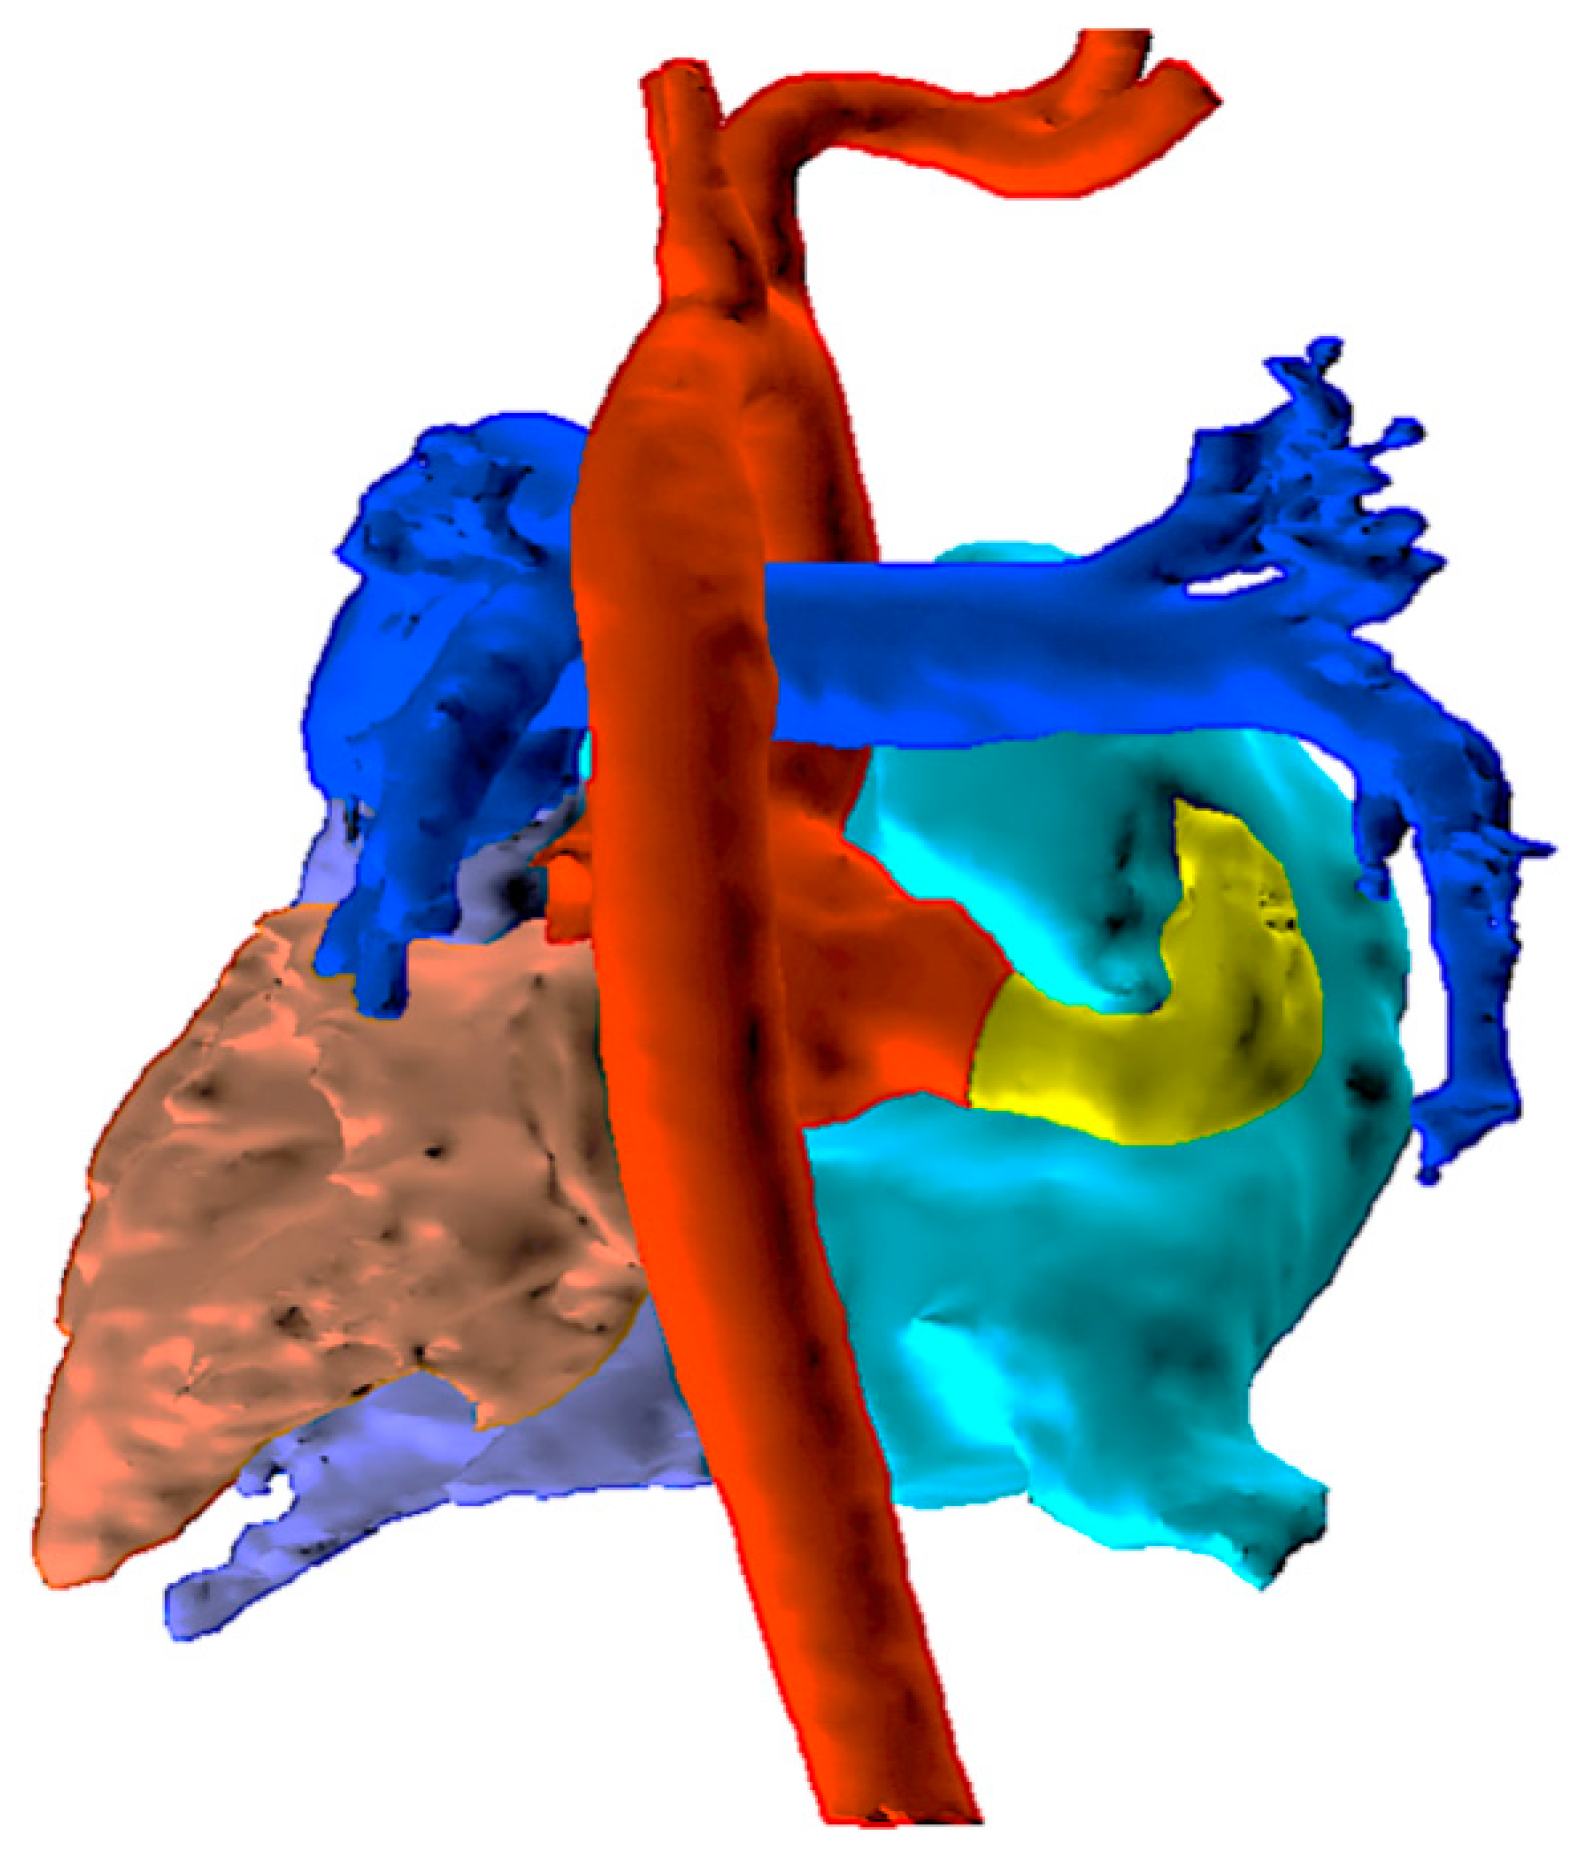

An echocardiogram revealed a dilated right atrium and ventricle with a normal left ventricular size and function. The aortic valve was tricuspid with mild aortic regurgitation. The noncoronary sinus of Valsalva (NCS) was dilated with a continuous turbulent flow between the NCS and the right atrium, which was approximately 8 mm in diameter. An atrial septal defect (ASD) (10 mm) was detected. To confirm the diagnosis of aorta–right atrial tunnel, a multidetector computed tomography angiography (CTA) was performed. CTA revealed that the left and right coronary arteries and branches were normal. The NCS was enlarged, from which a tortuous tunnel originated and terminated at the right atrial–superior vena cava junction (Fig. 1 and Fig. 2).

Figure 1: The course of ARAT in computed tomography across different imaging planes. (A) Axial view: An anomalous channel arising from the noncoronary sinus of Valsalva, coursing posterior to the right atrium. (B) Coronal reconstruction: The channel terminating at the right atrial–superior vena cava junction. (C) Sagittal reconstruction. *Aorta–right atrial tunnel.